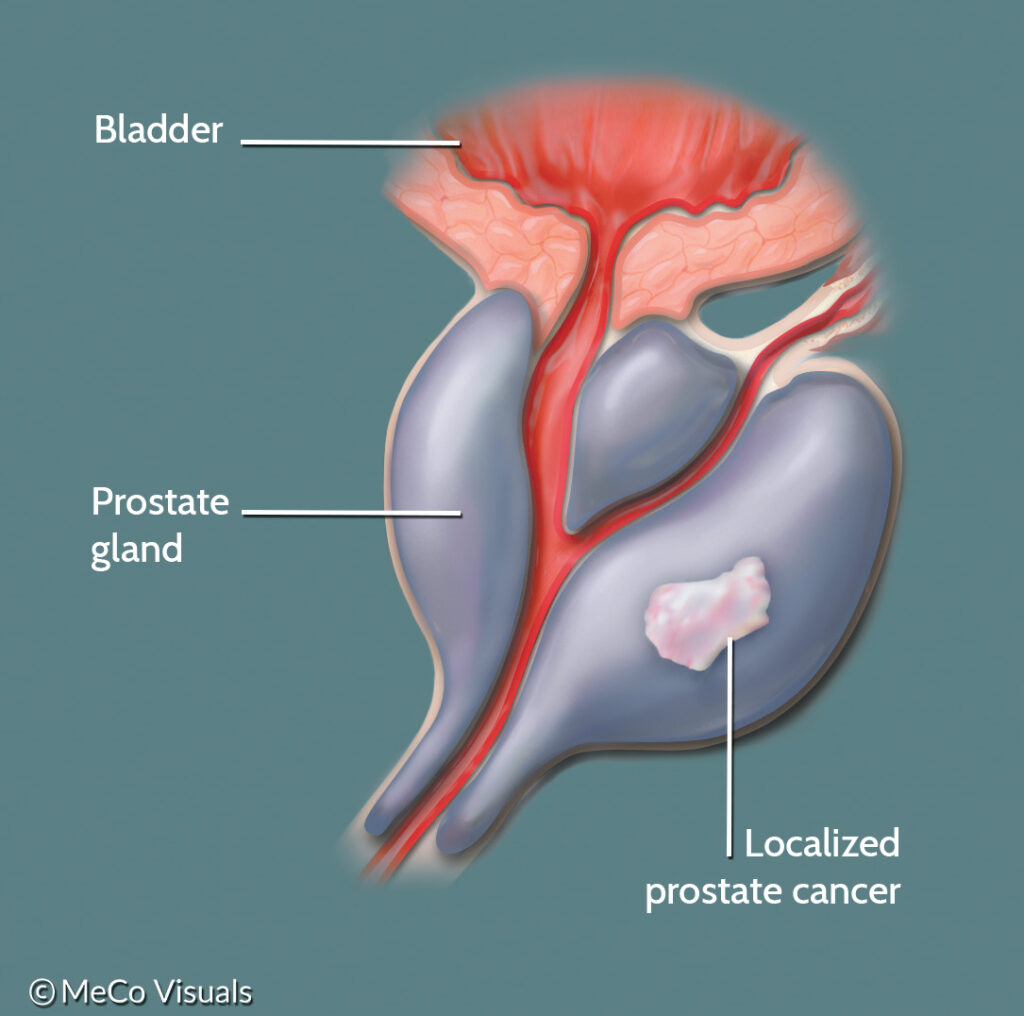

What is Localized or Locally Advanced Prostate Cancer? | PCF

Prostate Cancer Illustration Stock Illustration – Illustration of …